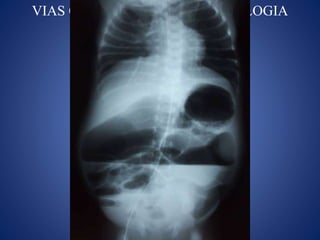

COMPLICACIONES

VIAS CENTRALES ENNEONATOLOGIA COMPLICACIONES